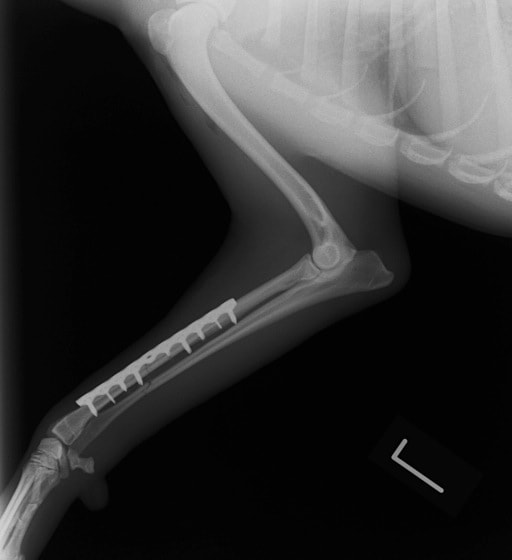

症例:交通事故による椎体脱臼

柴犬:9歳、避妊雌

交通事故直後、胸腰部に激しい疼痛、両後肢に完全麻痺を認め、シェフシェリントン徴候を呈していました。レントゲン検査において、第11-12胸椎間の脱臼が認められました。

脊髄の減圧、脊柱管の再構築・安定化を目的に、片側椎弓切除術およびMatrixMANDIBLE Plateによる椎体固定を実施しました。

隣接椎体を架橋するようにプレートを設置しました。

術後レントゲン写真